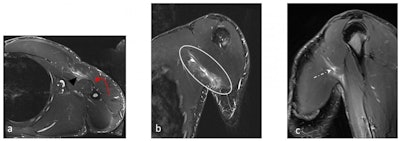

After lifting weights at the gym, a 33-year-old man presented with a partial articular supraspinatus tendon avulsion (PASTA) with superior labral anterior posterior (SLAP) tear. Coronal T1 and T1-weighted fat-saturated MRI arthrogram demonstrates a Type II SLAP tear; contrast entered the space between the superior labrum, with both vertical and horizontal component insinuating anteriorly towards the biceps tendon (straight white arrows). The biceps tendon is intact (yellow curved arrow). Also, note the PASTA lesion with tendon failure on the articular side of the supraspinatus tendon (red arrow)."Flexing the shoulder into an extreme overhead position increases the risk of injury-causing shoulder instability," they wrote. "Different types of labrum injuries have been previously reported including superior labral anterior posterior (SLAP) tears, anterior and posterior glenohumeral instabilities with subsequent impaired function besides the persistent pain that hinders adequate training and practice."

A 27-year-old man presented with a pectoralis major muscle injury, following a weight-training session in the gym. (a) Axial, (b) Coronal, and (c) Sagittal STIR images. Partial tear is visible at the myotendinous junction (black arrowhead and circle), mostly involving the sternal head with muscle fiber retraction. Edema is noted at the distal muscle fibers (white dashed arrow) but no complete tears. Preserved common tendon insertion at the humerus (red arrow).Rupture of the biceps tendon is more common, and proximal rupture of the long-head tendon has also been reported. "Both ultrasound and MRI are helpful in determining biceps rupture, whether partial or complete, tendon retraction, the presence of hematoma, myotendinous junction, and muscle belly and importantly assessment of associated injuries like rotator cuff tendon or labrum tears."